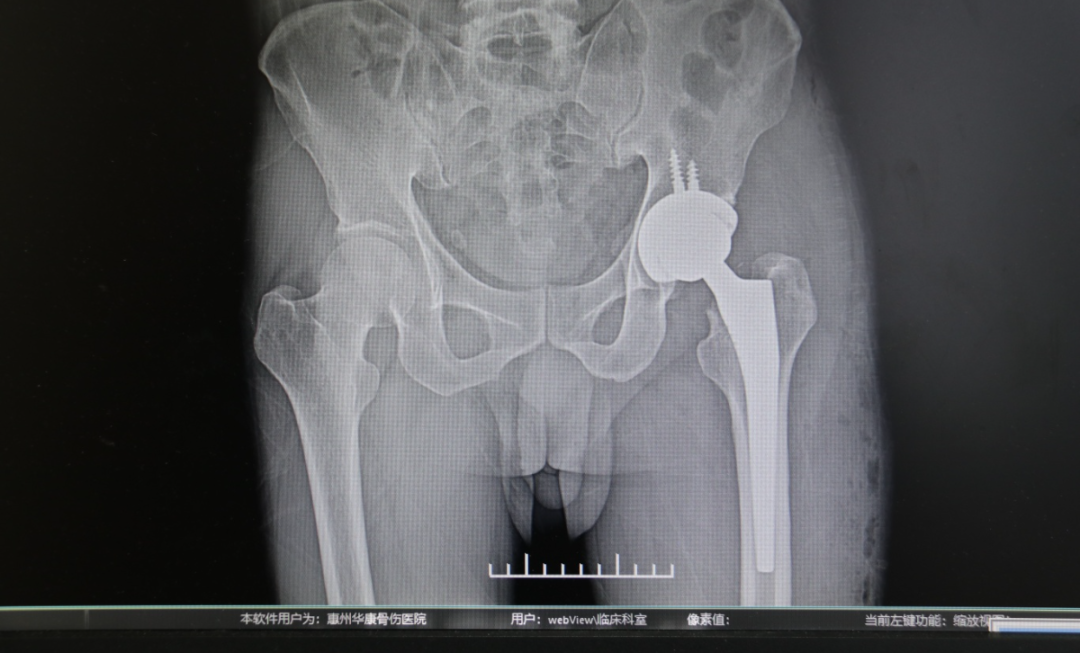

入院后,患者完善术前相关检查,排除了手术禁忌。伍见锋主任团队制定了详尽的手术规划,手术顺利进行。术后,在医护人员的精心照料下,患者第二天开始下地活动并进行康复训练,仅仅3天,疼痛逐渐消退,髋关节的活动度也基本恢复到正常水平,在助行器辅助下自如行走。